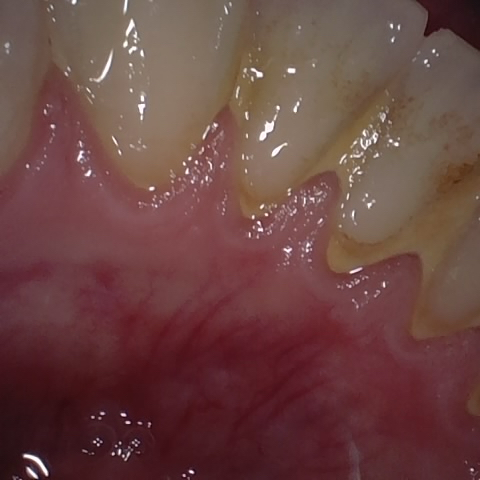

Annotated as "Good"

Original Image Rendering Image